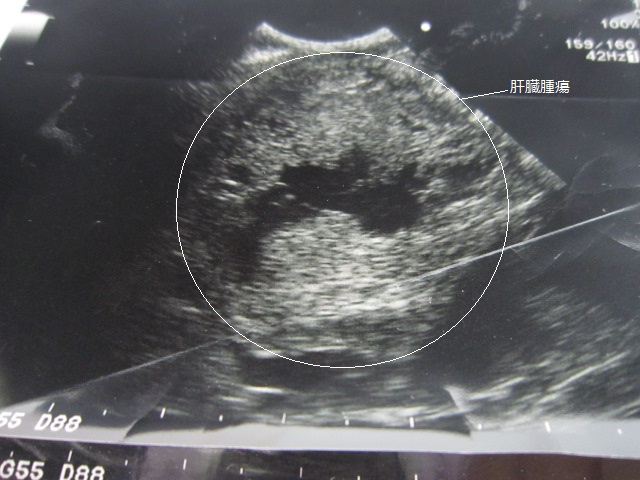

肝臓のあたりを超音波検査しました。

腫瘍が認められます。